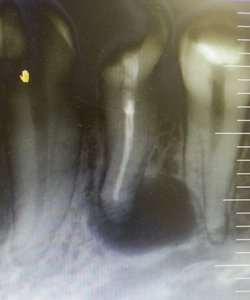

Образовался флюс, открыли канал, рассекли десну, выпустили гной, поставили дренаж, назначили полоскание содой. Прошло пять дней. Прихожу к доктору, ковырнула иголкой в зубе, не болит. Сказала, у вас киста, надо делать операцию. Не поверил, сходил в другую клинику, сделали снимок, посмотрели, говорит доктор, нету там никакой кисты. Пошел в третью клинику, показал снимок, показал зуб - прочистили, промыли, кисты не нашли.

Кисты, конечно, тут нет, но обширное воспаление и, как следствие, обострение периодонтита, наблюдается. Данную проблему можно разрешить консервативным методом лечения, то есть через канал. Обратитесь к грамотному терапевту.